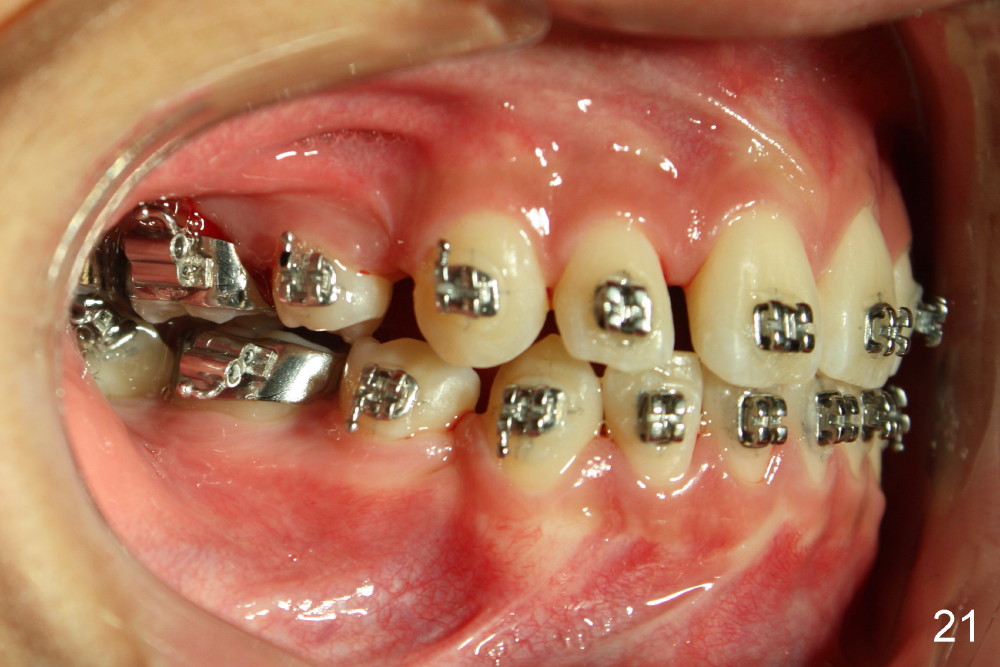

A 13-year-old boy has severe crowding (Fig.1-5). Four of the first bicuspids were extracted on 02/17/2014. Full mouth brackets or bands (except #18) were placed on 03/27/2014. Alignment improved 2 months later (Fig.11, 05/24/2014). The upper 18 ss wire was modified (Fig.12), and fixed with alastiks (Fig.13,14). One month later (07/01/2014), local alignment also improved (Fig.15); the upper modification is confined to one tooth.

Four and a half months post bracketing (Fig.21-25), what do you find and what should be done next?